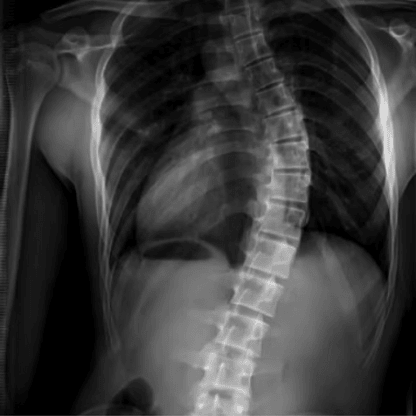

WHAT IS SCOLIOSIS?

Scoliosis is a curvature or deformity of the spine seen when looking from behind, where the spine should be straight, it curves.

Sometimes this curvature is obvious. Other times it’s subtle and goes unnoticed.

Tragically, scoliosis is rarely obvious at its onset, at the very stage when it may still be corrected.